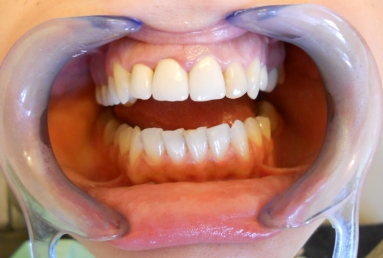

Before treatment: three porcelain fused to metal crowns on the right lateral incisor and on the two central incisors, left lateral incisor has a big composite filling and an old root canal treatment. The patient will receive full ceramic crowns on all four upper incisors.